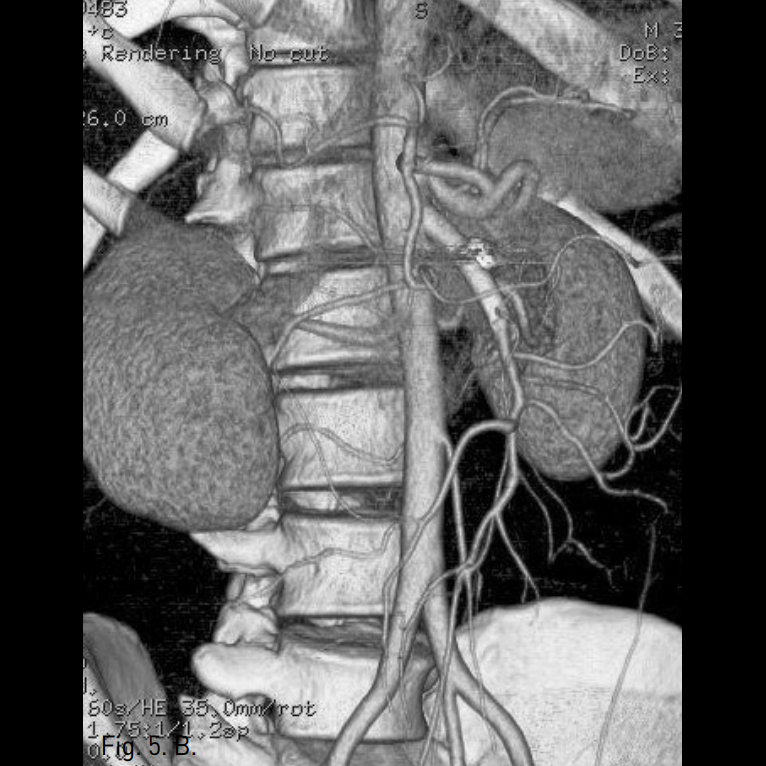

시술 전 CTA상 상장간막동맥 근위부에 직경 10mm 크기의 박리성동맥류가 확인되었고, 상장간막동맥은 벽내혈종으로 인해 혈관 직경은 12mm로 커지고 내강은 3mm로 협착소견을 보였다(Fig. 1A-C).

Fig. 1

A-C. Initial CT scan (A) shows dilated SMA with circumferential intramural hematoma and stenotic true lumen (arrow). Sagittal reconstructed MIP image (B) and volume rendered 3D CTA (C) show 1cm sized dissecting aneurysm (arrow hed) at proximal SMA and diffuse narrowing of true lumen.